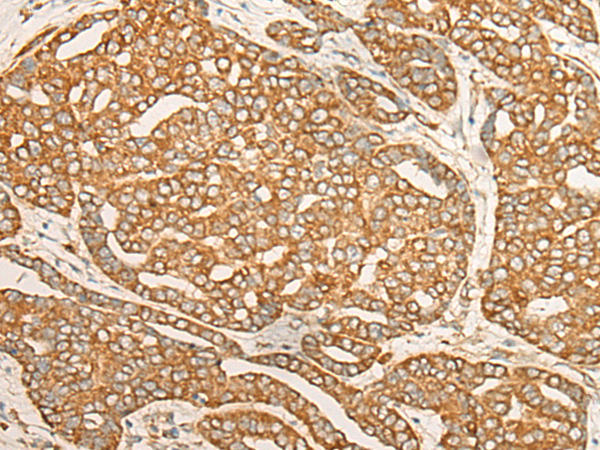

DARS1 |

aspartyl-tRNA synthetase 1 |

IHC positive control: |

Human liver cancer |

IHC Recommend dilution: |

30-150 |